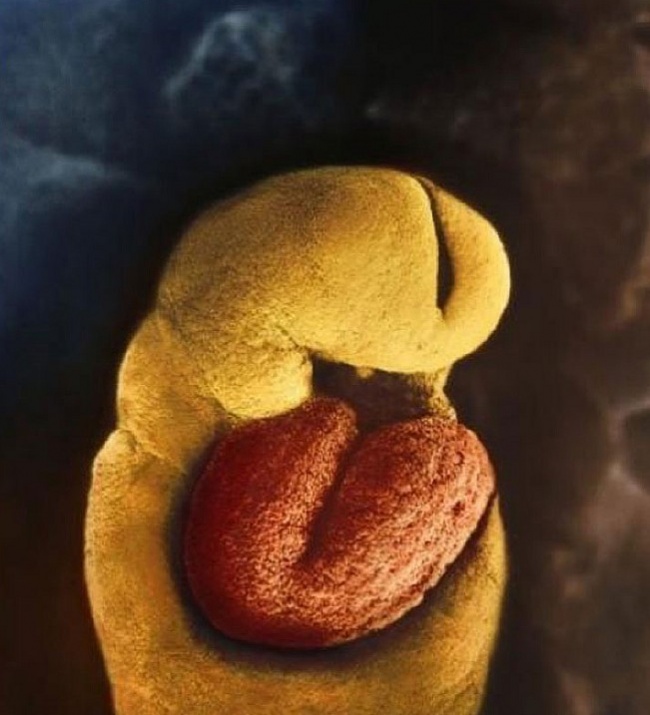

8 You can see the brain has started to develop

9 By the 18th day of development, the fetus’ heart begins to beat

10 28 days after fertilization

11 After 5 weeks. You can now distinguish the face with holes for eyes, nostrils and a mouth

12 40 days of development. The exterior cells of the fetus join with the loose surface of the uterus wall to form the placenta

13 8-week-old embryo. The fetus is well protected in the fetal sac